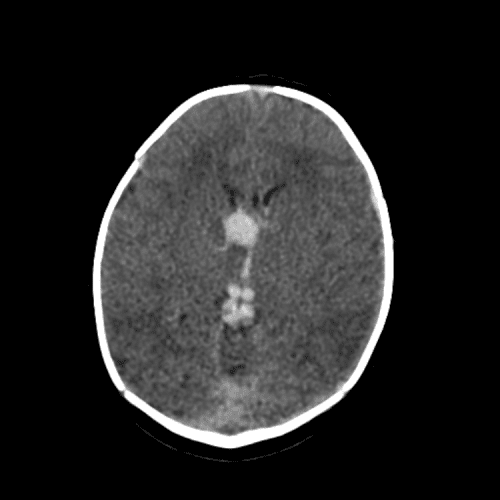

Basilar artery thrombosis